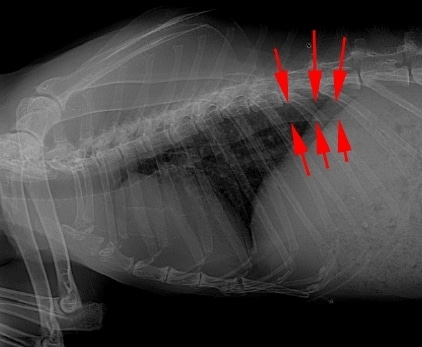

- Lors de maladies rénales, des ulcérations gastro-intestinales sont possibles, ainsi qu'une stase digestive suite à la déshydratation. Une anémie peut venir compliquer la maladie rénale avec un pronostic sombre. Chez le lapin, l'hypercalcémie liée à l'insuffisance rénale peut aboutir à la formation de calcifications à différentes localisations comme l'aorte, pouvant favoriser l'apparition d'une maladie cardiaque.

Calcification aortique visualisée à la radiographie (1)